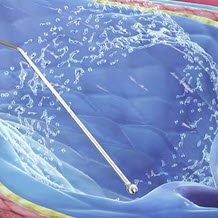

BIOPSY